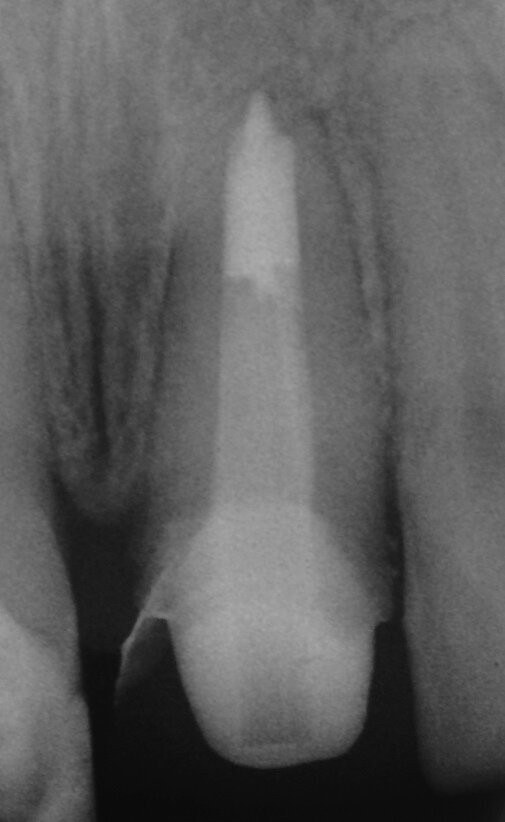

La perforazione accidentale della camera pulpare o del canale radicolare modifica in modo significativo la prognosi del dente. La riparazione della perforazione con un materiale sigillante biocompatibile come MTA può salvare i denti compromessi (Mente et al. 2014) (Figg. 3a-3e).